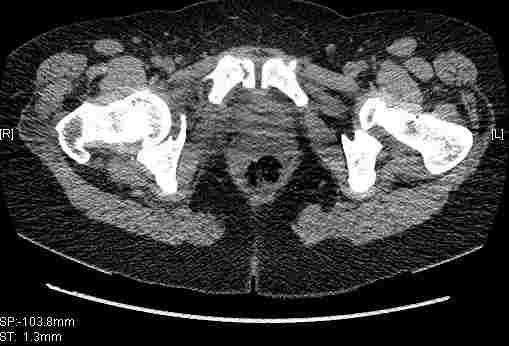

Удалось сегодня вывести пациентку в соседнюю больницу, где есть кт. Срезы сделаны только горизонтальные.